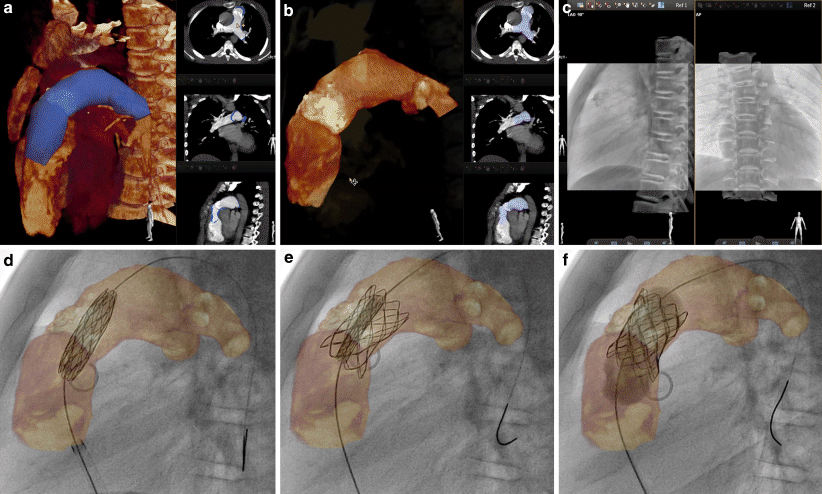

Application of VesselNavigator is based on four steps: segmentation, planning, registration and live guidance (Fig. 1; [13, 14]). In the first step, the application automatically creates a volume rendered 3D reconstruction from a raw CT or MRI dataset. Next, manual segmentation is performed by highlighting and selecting the desired region of interest on the 3D reconstruction or orthogonal MPRs. The second stage enables planning of the procedure by placing marking rings/points, taking measurements and selecting and storing the best angulations for the attempted intervention. The third stage includes fusion of live fluoroscopy and the manipulated 3D reconstruction. After storing fluoroscopy images in two, min 30° separated projections, vessel borders visualised with injection of a small amount of contrast medium or internal markers such as bony structures, shadow of the heart and great vessels, calcifications or previously implanted devices, serve as reference points for fusion. Finally live guidance of the procedure is performed with 3D roadmap overlaid and presented in several rendering modes with or without marking rings/points.

VesselNavigator assisted percutaneous pulmonary valve implantation. Automatic three-dimensional (3D) reconstruction (a, left panel) and row scans (right panels) from pre-registered computed tomography were manipulated to outline the conduit and the proximal pulmonary arteries (b). In addition to bony structures, heavy conduit calcifications were utilised to enhance manual 3D image fusion with live fluoroscopy (c). The 3D roadmap was utilised to guide creation of the landing zone (d) and subsequent implantation (e, f) of a Melody valve (Medtronic Inc.)